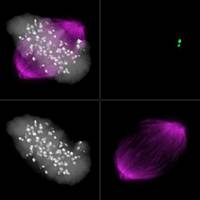

Biowissenschaften - 28.01.2016

Fehler in der Bildung von Nervenzellen können zu neuronalen Entwicklungsstörungen wie beispielsweise Mikrozephalie, Kleinwuchs des Gehirns, führen. Das Team von Prof. Clemens Cabernard vom Biozentrum der Universität Basel hat nun ein Protein untersucht, das an der Entstehung der Mikrozephalie beteiligt ist.